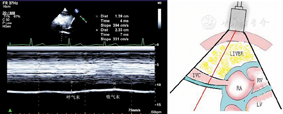

(1)胸骨旁左心室长轴切面(图1图2图3)

胸骨旁左心室长轴切面引导2a区M型超声心动图,显示收缩末期和舒张末期室间隔厚度、左心室内径和左心室后壁厚度测量方法